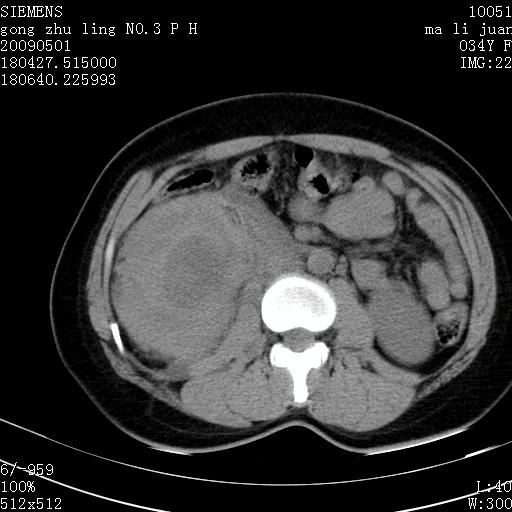

标题: CT19733:右肾碎裂 [打印本页]

标题: CT19733:右肾碎裂

青年女性,骑摩托车摔伤。

右肾碎裂伤,包膜下血肿。

术中仅见右肾碎裂,肾蒂血管未见断裂。